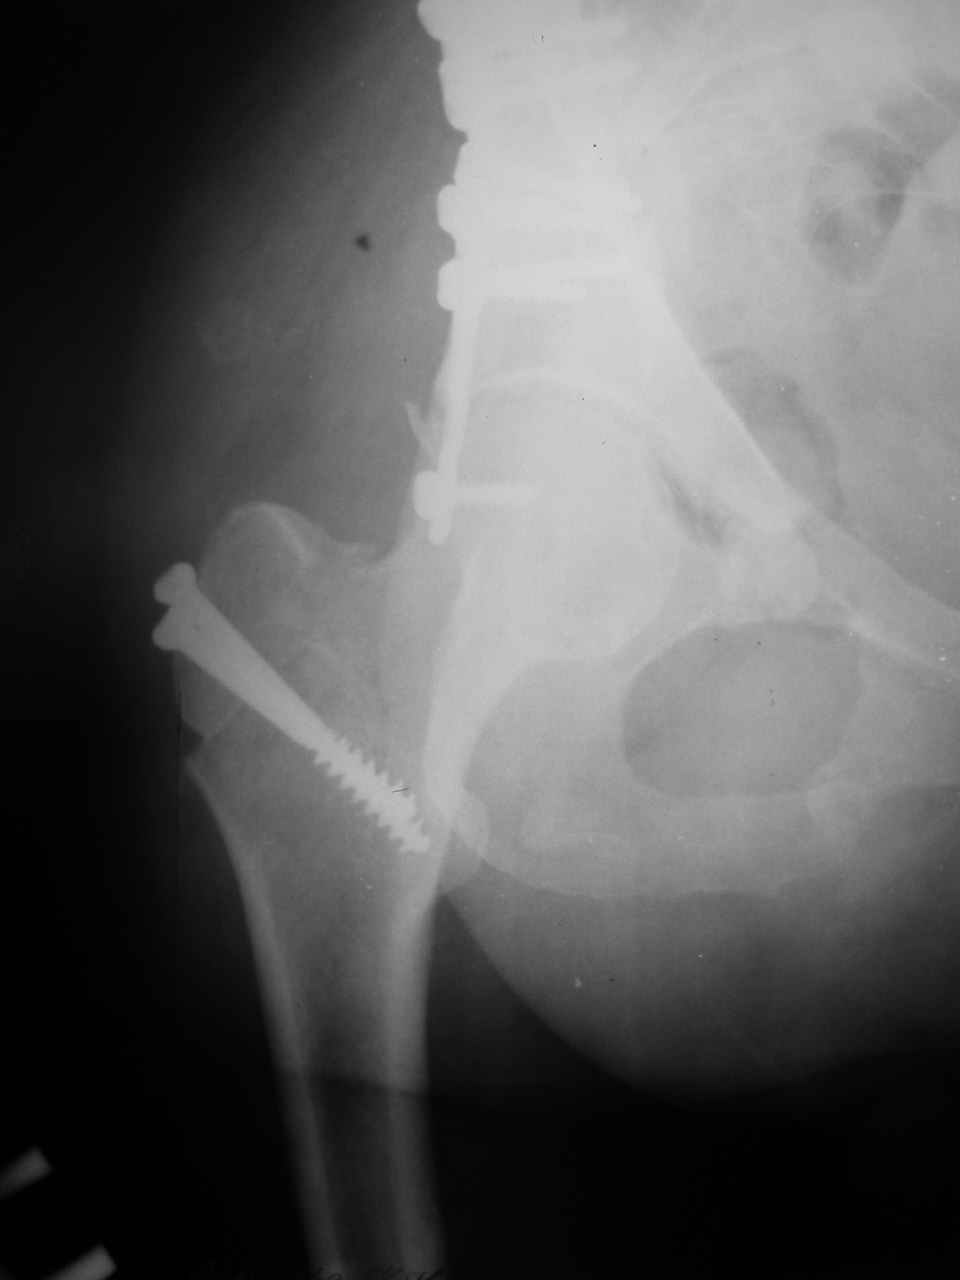

Спасибо за комментарии и рекомендации. Откровенно говоря, больного я прооперировал на прошлой неделе, через 5 дней после аварии и проблем с ним пока никаких нет, на удивление при достаточно обширной диссекции (илиофеморальный доступ) болей практически нет, так что больной самостоятельно садится в кровати, выполняет активные движения в оперированном суставе, сгибая до 60 градусов пока, далее с ассистенцией.

Причиной обращения к сообществу были возникшие непосредственно после операции сомнения и разочарования полученным качеством репозиции: а надо ли было трогать перелом вообще, репозиция передней колонны технически была очень сложна для меня, хотя реконструкции была в той же последовательности, что Д-р А.В.Рунков рекомендовал, в какой-то момент безуспешных манипуляций стал думать о *вторичной конгруэнтности*, которую не так давно обсуждали на

форуме и скелетном вытяжении. С репозицией и фиксацией задней колонны и отдельно задне-верхней стенки впадины проблем не возникло. Послеоп. Рг граммы в приложении. Если возникнут какие-либо дополнения или поправки - был бы признателен.

А какой отдел вертлужной впадины более важен передний или задний? Чем был обусловлен выбор доступа к суставу? Проще говоря, почему вы пошли передним доступом на двухколонный перелом? Мне понятны ваши сомнения, когда не удется сделать все что хотелось бы. В данном случае доступ должен быть чрезвертельным боковым (как и советовал Рунков) или двумя доступами.

Илеофеморальный доступ не совсем передний и сравнительно с илеоингвинальным, и Кохера-Лангенбека открывает весь наружный таз кроме самых передних отделов лонных костей, фиксацию которых я не ставил в задачу. Обширность диссекции, большая длительность операции и более высокий риск гетерооссификации - отрицательные моменты в обмен на возможность легче ориентироваться.